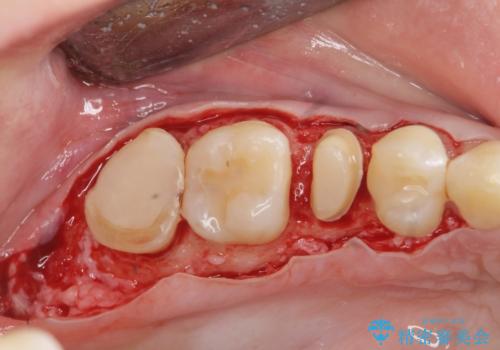

放置した虫歯を外科を行い抜歯を回避

- 放置していた虫歯が欠け、いよいよ怖くなり治療を希望され来院されました。

虫歯は、その進行度によりさまざまな治療法が提案されますが、

エナメル質・象牙質に限局する虫歯 →インレー修復

歯の神経に達する虫歯 →根管治療 クラウン補綴

歯ぐきよりも深い虫歯 →歯周外科による歯周環境の整備

を適宜行うことで良好な結果を得ることができます。

症状に応じて適切な処置を行ったことで、抜歯を回避し良好な結果を得ることができました。